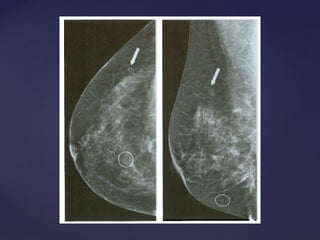

Padrão mamográficoPadrão mamográfico

Descrição Acurácia Diagnóstica

Lipossubstituídas (até 25% de tecido

glandular)

Muito alta

Parcialmente lipossubstituídas (26 a 50% de

tecido glandular)

Alta

Densas e heterogêneas

(51 a 75% de tecido glandular)

Limitada

Muito densas (>75% de tecido glandular) Limitada